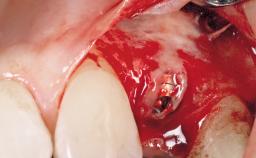

A 30-year-old female patient was referred to the office for the treatment of tooth 11. Her chief concern at the initial visit was to inquire, “Why is my tooth pink?” Upon clinical examination, it was determined that tooth 11 had a previous history of trauma and that the clinical crown had become noticeably pink in color as a result of internal resorption. This diagnosis was confirmed radiographically, indicating a large radiolucency involving the central and distal portions of the clinical crown. It was determined that restoration of this tooth was not possible, and that extraction was indicated. The presence of a mid-line diastema, which the patient wanted to reproduce, directed the treatment plan for tooth replacement utilizing a dental implant.

Type of Implants One-Piece|Reduced-Diameter

Placement Protocol Immediate implant placement

Socket Morphology Single-root socket

Socket Integrity Sufficient, with intact bone walls